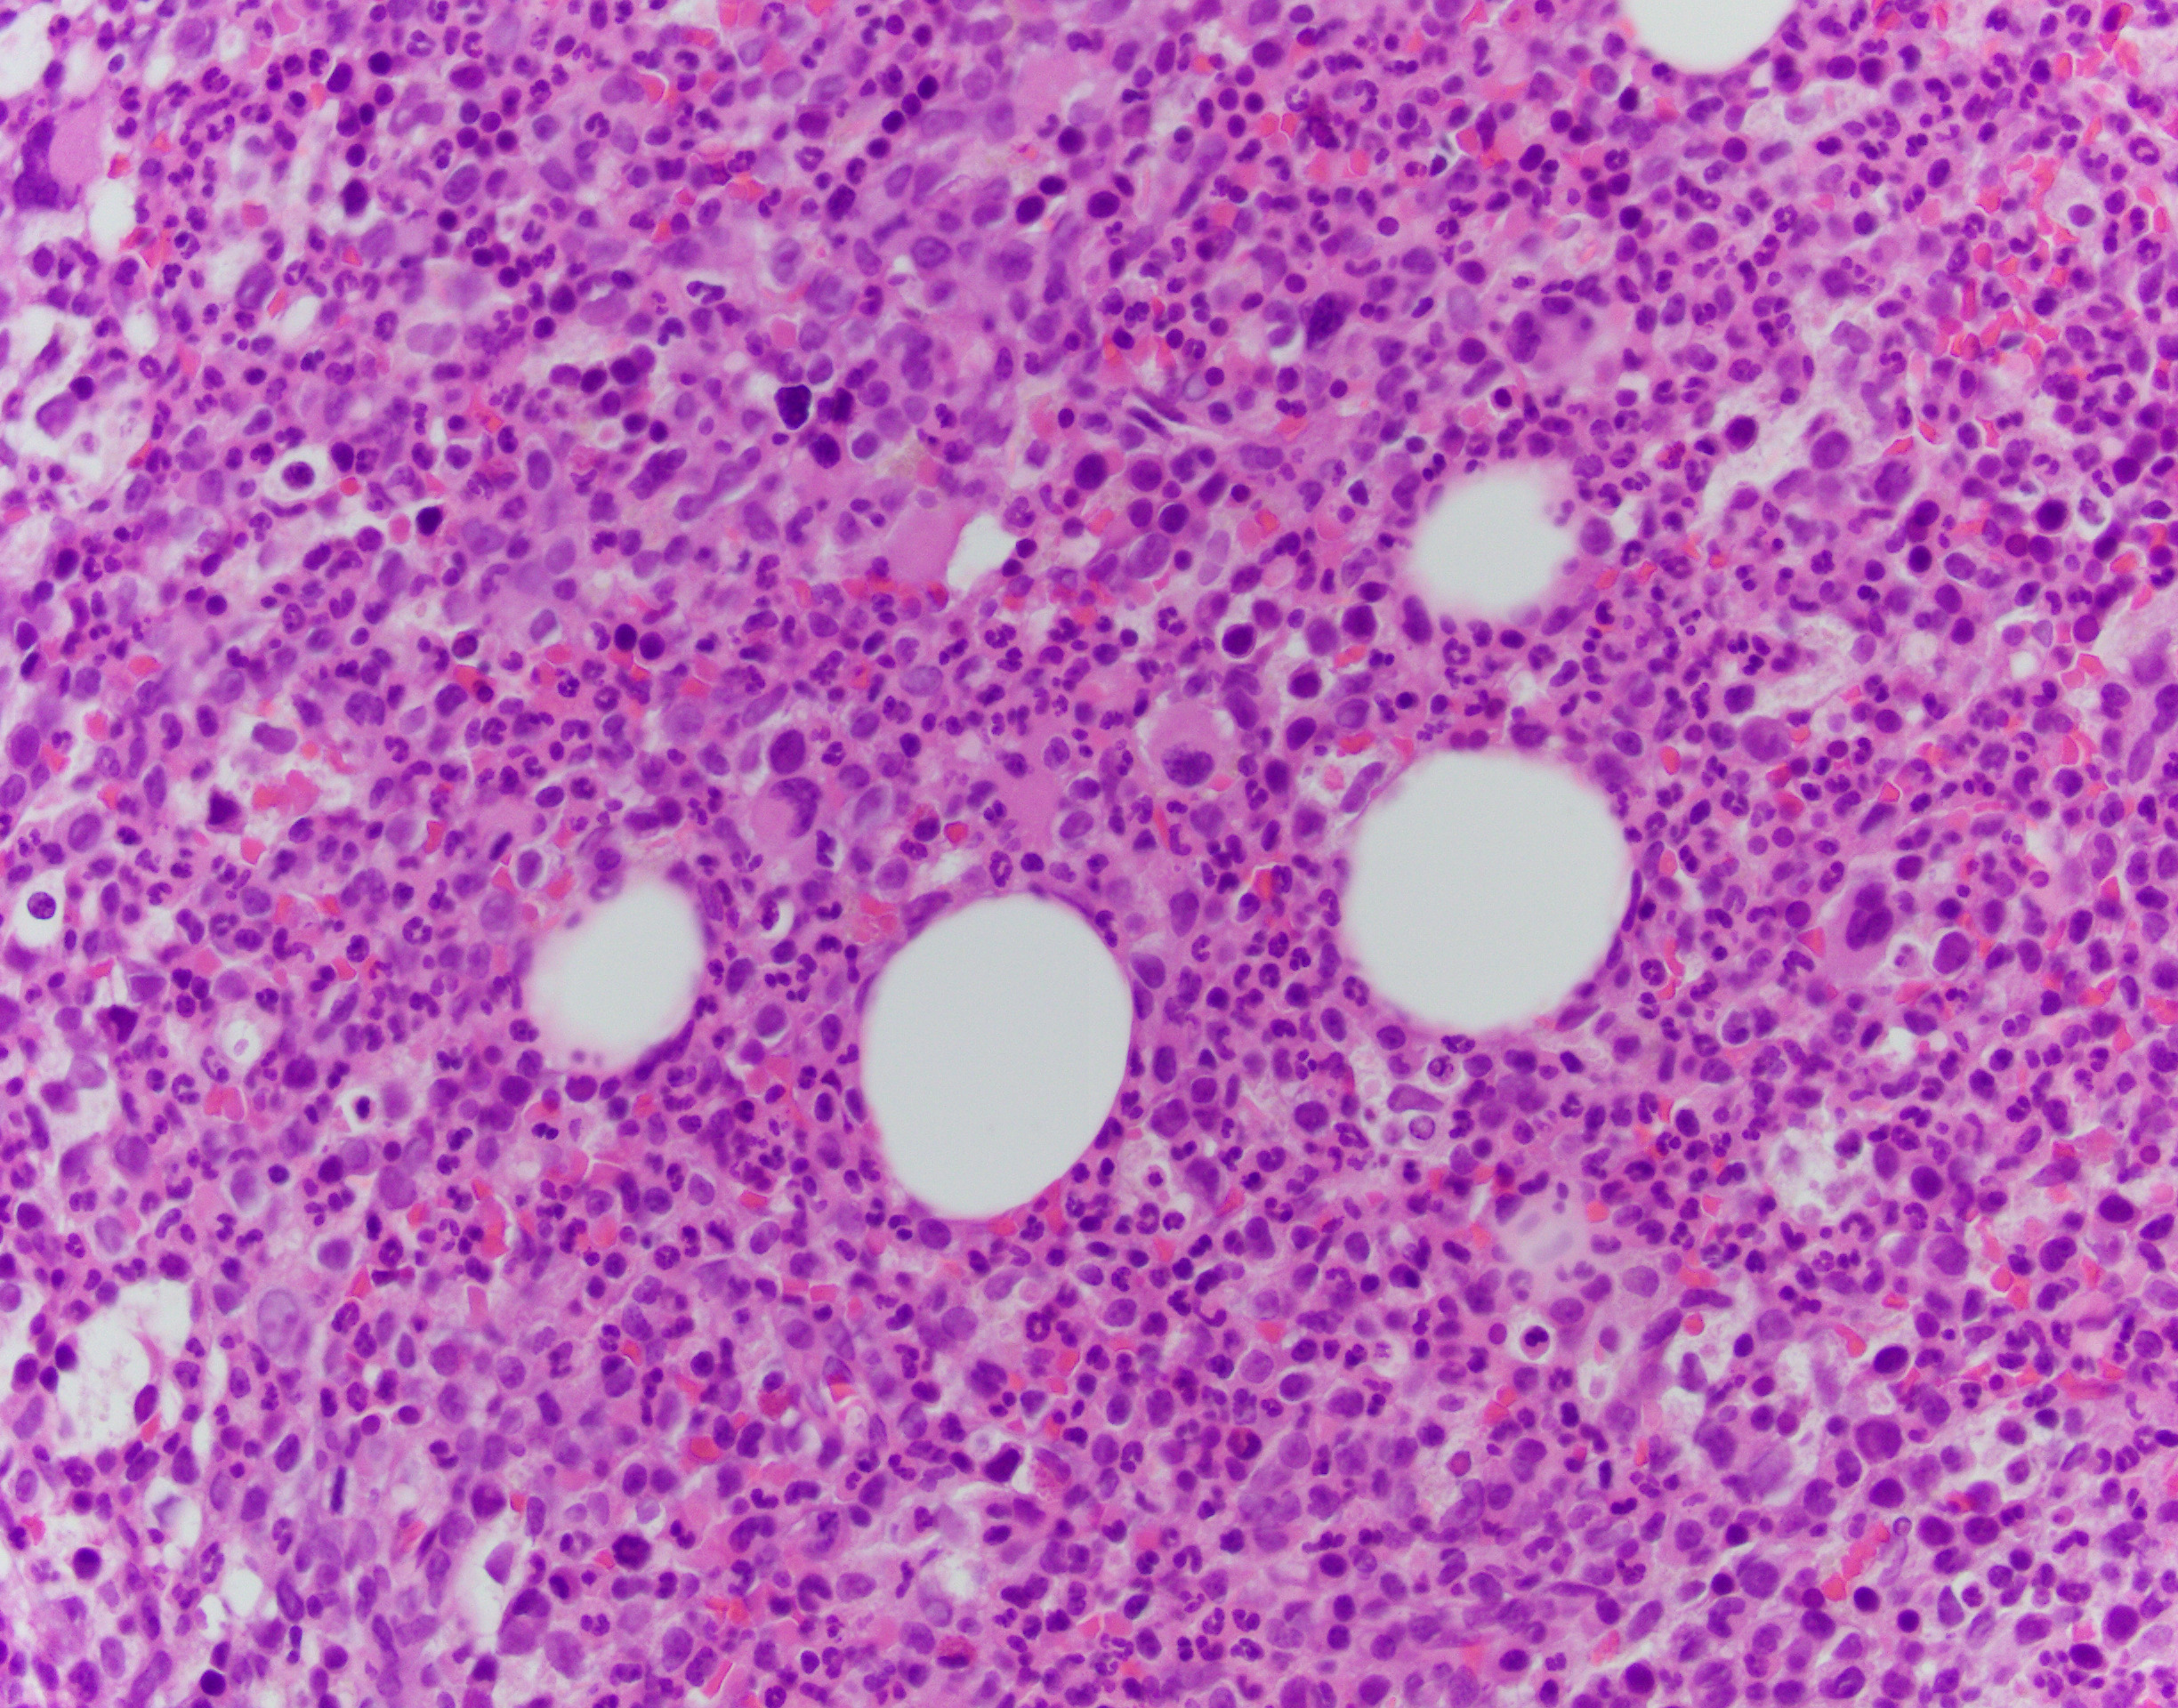

The patient is a 76-year-old male with anemia (Hgb 8.6) and thrombocytopenia (15,000/microliter). Of note, serum copper levels are low. Photomicrographs of the bone marrow aspirate and biopsy are provided.

The patient's bone marrow biopsy shows a hypercellular marrow with dysmegakaryopoiesis and no overt increase in blasts on routine stains. In a patient with cytopenias and this morphology, the diagnosis is unfortunately rarely straightforward. The differential diagnosis of entities that can cause morphologic dysplasia is long and includes infection, medications, autoimmune processes, nutritional deficiencies, and myeloid neoplasms. Follow-up of concurrent cytogenetic and molecular tests is essential for further classification; however, a normal karyotype does not fully rule out a myelodysplastic syndrome.

Copper deficiency is notorious for being a mimicker of MDS, and supplementing copper and observing the patient's CBC and possibly repeating a biopsy may be necessary in this patient. While definitely a possibility, this case is not classic for pure copper deficiency. Thrombocytopenia is less common, and the classic morphologic findings in copper deficiency are dysplasia in the erythroid lineage with cytoplasmic vacuoles in the erythroid and granulocytic lineages.